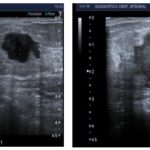

Anexo 3. Imágenes CMTN en resonancia magnética

Características en RNM del CMTN

En los resultados de las características en resonancia magnética, se debe tener en cuenta que de las 17 pacientes solo se dispone información de 8 resonancias magnéticas realizadas en centros periféricos. Esto representa el 75% de la muestra, equivalente a 8 casos.

De estos casos se destaca que informan una cantidad de tejido fibroglandular tipo B, aunque no describen el realce parenquimatoso de fondo ni hallazgos asociados.

En lo que respecta a la descripción nodular, se encontró que en el 77,7% de los casos (7 de 8) el nódulo se reportó como redondeado, seguido de la forma ovalada.

Los márgenes del nódulo en 7 casos se describen como circunscritos y solo en 1 caso se reporta como espiculado.

Según lo referido realce interno del nódulo, 5 casos presentaron realce heterogéneo periférico y 3 casos mostraron un realce en forma de anillo.

Finalmente, en la evaluación de la valoración de las curvas cinéticas, se notó que en la fase inicial los 8 casos tenían una fase rápida. En la fase tardía, 6 de los casos presentaban un patrón de wash out, mientras que 2 casos mostraban un tipo de realce en meseta.

Los resultados de resonancia magnética mostraron hallazgos consistentes con la literatura, incluyendo el realce periférico, nódulos heterogéneos y curvas cinéticas tipo 2 y 3. A pesar de la limitada disponibilidad de resonancias magnéticas en centros periféricos, estos hallazgos respaldan la utilidad de esta técnica en la evaluación de tumores mamarios.

Los hallazgos imagenológicos en mamografías, ecografías y resonancias magnéticas en pacientes con CMTN concuerdan con la bibliografía médica actual, lo que respalda la utilidad de estas técnicas para el diagnóstico y caracterización de los CMTN.